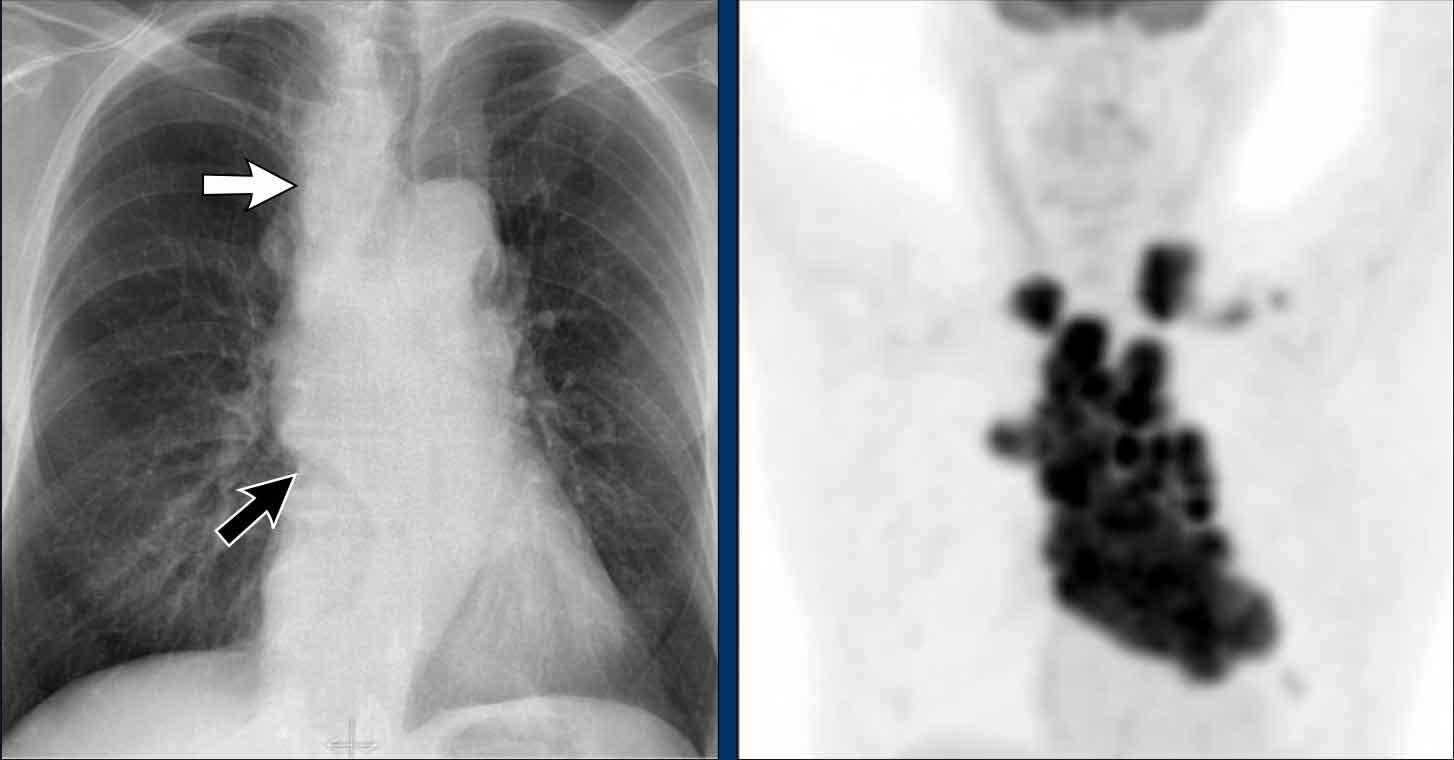

Dịch chuyển đường azygô-thực quản (2) – Hạch to dưới carina

Một nguyên nhân thường gặp gây dịch chuyển đường azygô-thực quản là hạch to dưới carina (trạm 7).

Trên phim X-quang ngực, lưu ý hình ảnh đường azygô-thực quản bị đẩy lên trên ngay dưới carina, phù hợp với hình ảnh hạch bạch huyết dưới carina to (mũi tên đen).

Ngoài ra còn thấy hạch to cạnh khí quản phải, đẩy dải cạnh khí quản phải (mũi tên trắng) và làm lệch khí quản sang trái.

Tiếp tục với hình ảnh PET-CT…

Hình ảnh PET

- PET-CT cho thấy hình ảnh hạch to tăng chuyển hóa lan rộng ở trung thất và vùng cổ, rõ ràng hơn so với trên phim X-quang ngực.

- Các hạch bạch huyết vùng cổ có liên quan — đây là phát hiện quan trọng vì chúng có thể tiếp cận được để sinh thiết.

Tiếp tục với hình ảnh CT và siêu âm…

Hình ảnh CT

- CT có thuốc cản quang cho thấy hạch to dưới carina kích thước lớn, đẩy lệch ngách azygô-thực quản và chèn ép nhĩ trái.

- Sinh thiết hạch vùng cổ xác nhận ung thư phổi tế bào nhỏ.